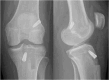

Graft-tunnel mismatch (GTM) is a known technical challenge that can occur with anterior cruciate ligament reconstruction when using a patellar tendon autograft. Two-incision anterior cruciate ligament reconstruction is a well-established technique with excellent outcomes and can serve as an excellent tool to prevent GTM. Traditionally, 2-incision femoral tunnel drilling has been performed using an over-the-top guide through a lateral incision, but more modern retrograde reamer guides can allow this to be done percutaneously. We detail how a minimally invasive 2-incision femoral tunnel drilling technique can be used in patients with patellar tendon lengths that are longer than average to avoid GTM.